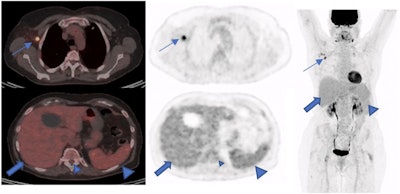

A 73-year-old woman with a suspicious lung nodule was referred to our division for F-18 FDG PET/CT exam. She was vaccinated four days before PET/CT. The lung nodule did not show any pathological FDG uptake; however, high tracer activity was detected on her right arm, where she was injected, and multiple hypermetabolic lymph nodes in the right axilla (arrows). Moreover, PET/CT showed high tracer activity in the liver (black arrows), spleen (triangular arrows), and bone marrow (small triangular arrows) as the result of systemic immune response after vaccination. The tracer defect in the liver was due to the known cyst. (A) fusion scan, (B) PET, (C) maximum intensity projection. Image courtesy of Scientific Reports.